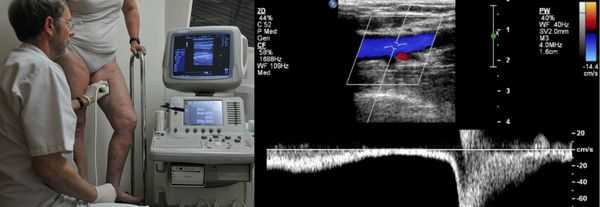

На приеме у врача - флеболога в Центре амбулаторной хирургии, пациенту ставится диагноз на основании анамнеза, жалоб пациента, а также результатов исследования. Основной способ инструментального обследования — дуплексное ультразвуковое сканирование. В нашей клинике врачи функциональной диагностики во время проведения исследования не только подтверждают наличие ХВН, но и помогают хирургам определиться с объемом поражения венозной системы и выбором тактики дальнейших действий. В отдельных случаях может лечащим врачом может быть назначено дуплексное ангиосканирование или рентгенконтрастное исследование (флебография).

Проведение диагностики ХВН на ранних стадиях способствует ускорению лечения. При диагностике важно определить стадию заболевания. После общего клинического осмотра врач проводит дуплексное ангиосканирование вен нижних конечностей, чтобы определить тактику лечения. Дуплексное ангиосканирование поможет оценить состояние исследуемых сосудов, увидеть места их сужений или расширений, а также выявить тромбообразования.

Одним из самых доступных методов диагностики данного заболевания является УЗИ, главным преимуществом которого является многоразовость применения без рисков для здоровья, безболезненность, а также возможность выявить нарушения в текущей работе венозного аппарата. [3]

Для получения лучшего результата обследование рекомендуется проводить во второй половине дня. Поскольку именно после дневной нагрузки на ноги можно провести более точную оценку состояния клапанов, диаметра вен и степени поражённости стенок. На тактику лечения влияет наличие тромба в просвете вен, который приводит к нарушению тока крови и несёт наибольшую угрозу для жизни пациента.

УЗДС дает полную картину причин ХВН

При УЗДС-обследовании врач получает трехмерное изображение сосуда, достоверную информацию о его функционировании, и может поставить объективный диагноз.